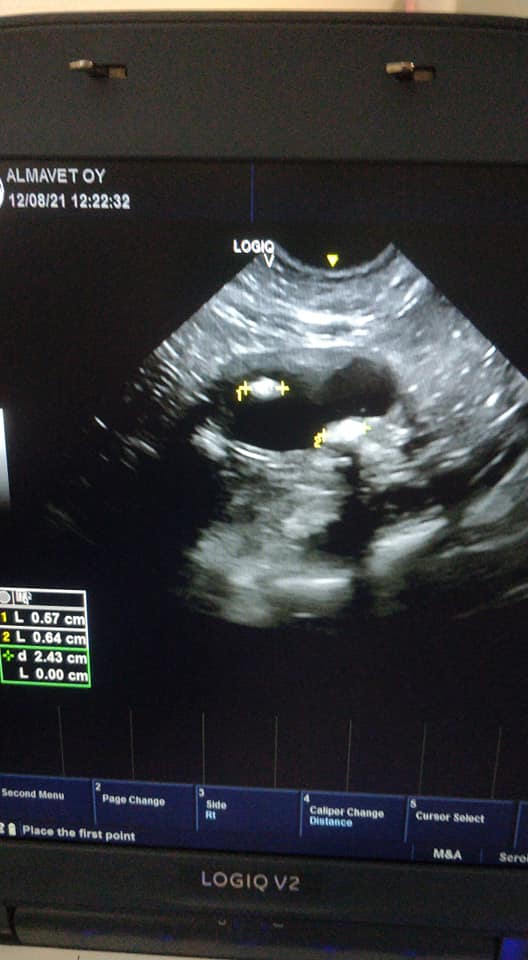

Alla on kaksi ultrakuvaa kissan virtsarakosta sekä yksi kuva mikroskoopin alla olevasta virtsan sedimentistä. Niille jotka eivät päivittäin katsele ultrakuvia rakosta tiedoksi, terve virtsarakko on ultrassa ohutseinäinen täysin musta pallo. Toisessa rakossa on runsaasti verta, toisessa virtsakiviä. Terveessä virtsassa ei myöskään näy mikroskoopissa paria solua ihmeempiä, joten jos näyte näyttää kuhisevalta suurkaupungin vilinältä niin jotain on meneillään (tässä näytteessä kyseessä oli virtsatieinfektio).